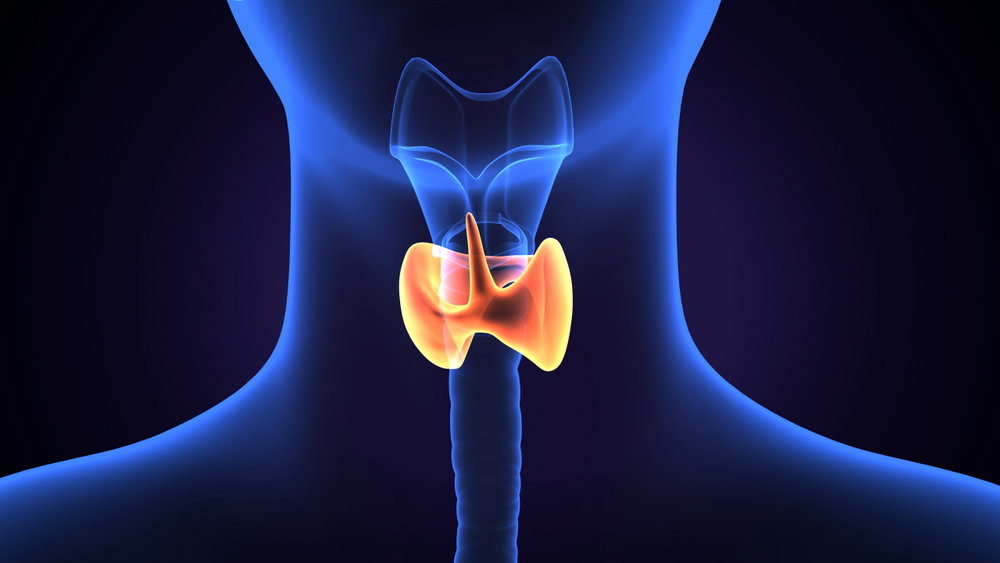

بهترین دکتر پرکاری پاراتیروئید تبریز + لیست 10 تایی